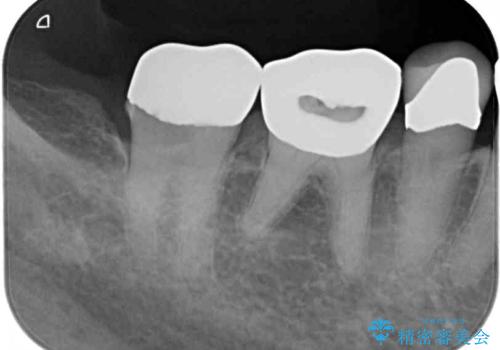

- 奥歯の銀歯に穴が空いてしみるとのことで来院された患者様です。

長年が経過して、徐々に穴が空いてきていたが、最近しみるようになったとのことでした。

痛みの感じ方に異常な所見は認められなかったため、オールセラミッククラウンにて補綴治療を行うこととしました。

銀歯を外したところ、非常に大きなむし歯が認められましたが、神経組織には及んでおらず、速やかにオールセラミッククラウンによる補綴治療を行いました。